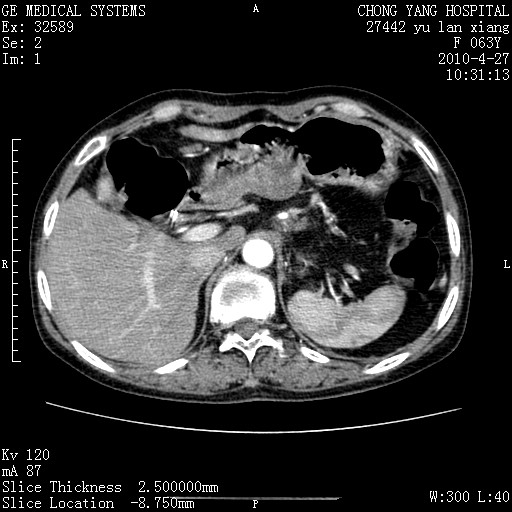

标题: CT26066:F63Y 上腹正中压痛半月,CA199:7400u/ml,MR示胰腺炎伴 [打印本页]

胰腺癌侵犯腹腔动脉干-分支、胃壁、左侧膈肌伴胰周及腹膜后淋巴结转移、胆囊切除术后。

胰腺癌侵犯腹腔动脉干-分支、胃壁、左侧膈肌伴胰周及腹膜后淋巴结转移、胆囊未显影。